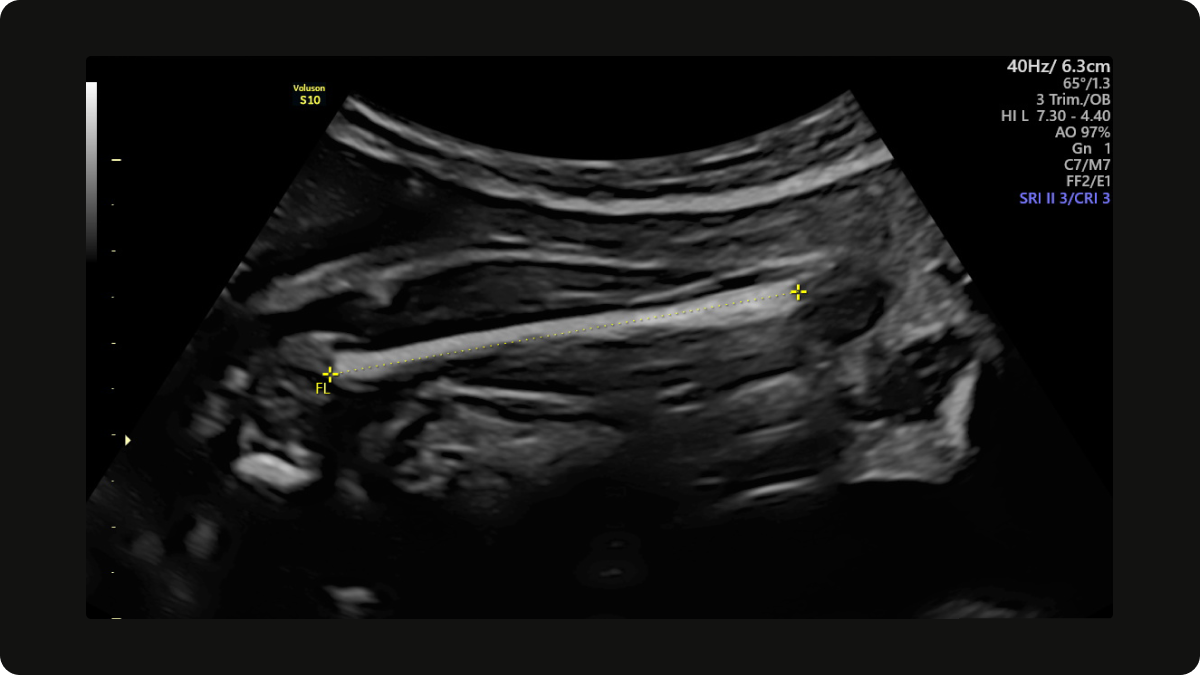

FL (Femur Length) meaning

Femur length is the length of your baby’s thigh bone. It's measured to identify short bones, but also to estimate baby's current weight.

If your baby's femur is short (outside of normal range), your sonographer will measure the length of the other femur and the length of both upper arms, shoulder to elbow. It's very important to note that an isolated short femur is likely normal, especially with petite parents.

A short femur, along with short upper arms (humerii), can be a sign of achondroplasia (dwarfism) and other skeletal abnormalities. Short femurs can also be a sign of Down's syndrome.

If a short femur is identified at your scan, further, more detailed investigation will be offered.

Femur length (FL) on a growth scan at 28 weeks gestation